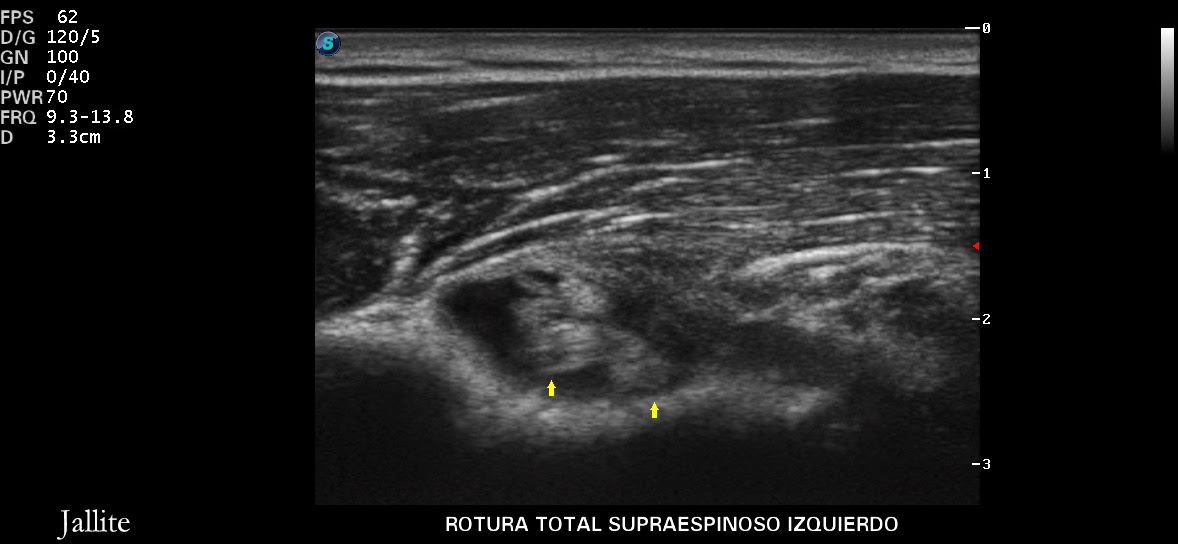

Sentencias De Incapacidad Permanente Por Rotura Del Tendón Supraespinoso, Incapacidad permanente por lesiones de hombro., 11.76 MB, 08:34, 49,493, Abogado Ramón Escribano Garés, 2018-06-04T07:30:27.000000Z, 3, Reparación artroscópica de las roturas del manguito rotador | Revista, elsevier.es, 1024 x 889, jpeg, WebLa actora reclama se la declare en situación de incapacidad permanente total derivada de accidente de trabajo. La contradicción requiere que las resoluciones que se comparan. WebIncapacidad por rotura del tendón del bíceps. Nota: El derecho a la prestación sólo debe concederse por una afección crónica. A efectos del VAC, “crónico” significa que la. WebPatologías de Incapacidad permanente total. Síndrome Subacromial Grado 3 dcho y Grado 2 Izq Rotura del Tendón Supraespinoso completa Tendinopatía Hombro Izq.., 20, sentencias-de-incapacidad-permanente-por-rotura-del-tendon-supraespinoso, Novedades y Muebles WebLa actora reclama se la declare en situación de incapacidad permanente total derivada de accidente de trabajo. La contradicción requiere que las resoluciones que se comparan. WebIncapacidad por rotura del tendón del bíceps. Nota: El derecho a la prestación sólo debe concederse por una afección crónica. A efectos del VAC, “crónico” significa que la. WebPatologías de Incapacidad permanente total. Síndrome Subacromial Grado 3 dcho y Grado 2 Izq Rotura del Tendón Supraespinoso completa Tendinopatía Hombro Izq..

WebCuando un trabajador sufre una rotura del supraespinoso, en primer lugar muy probablemente será declarado en proceso de incapacidad temporal (baja médica).. Web11 ZeilenPatologías de Incapacidad permanente total. Síndrome Subacromial Grado 3 dcho y Grado 2 Izq Rotura del Tendón Supraespinoso completa Tendinopatía. WebCuando la tendinitis deviene crónica, la conocemos con el concepto de tendinosis del supraespinoso. En esos casos, las dolencias suelen ser irreversibles. Muy. WebDERECHO: Rotura a espesor completo en el extremo distal del tendón del supraespinoso, atrofia en su vientre muscular y en menor grado en el infraespinoso.. Webse declaró a la demandante en situación de incapacidad permanente total, con derecho a percibir el 55% de la base reguladora de 1.408,14 euros al mes:- La. WebActualmente se han obtenido sentencias favorables de incapacidad laboral por síndrome subacromial, tendinitis de hombro y rotura del supraespinoso. Cuando el INSS ha. WebLo primero que tenemos que hacer es determinar cuál es la lesión que tenemos en el hombro. Para ello, habrá que acudir al médico y que nos haga las pruebas de.

WebIncapacidad permanente total por rotura supraespinoso ☝ Restricciones laborales por desgarro del manguito de los rotadoresEl dolor de hombro es una afección. WebIncapacidad permanente absoluta por rotura supraespinoso. Un desgarro del manguito de los rotadores puede dejarle en el banquillo durante varias semanas, pero con los. WebSentencias de Incapacidad Permanente. Casos de éxito de Campmany Abogados. En esta sección podrás encontrar cientos de ejemplos de sentencias de incapacidad permanente.